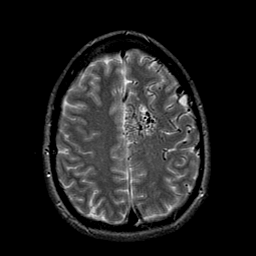

Vascular Malformation:T2-weighted MR #1 -- Slice #18

[Home][Help][Clinical] Slice 18